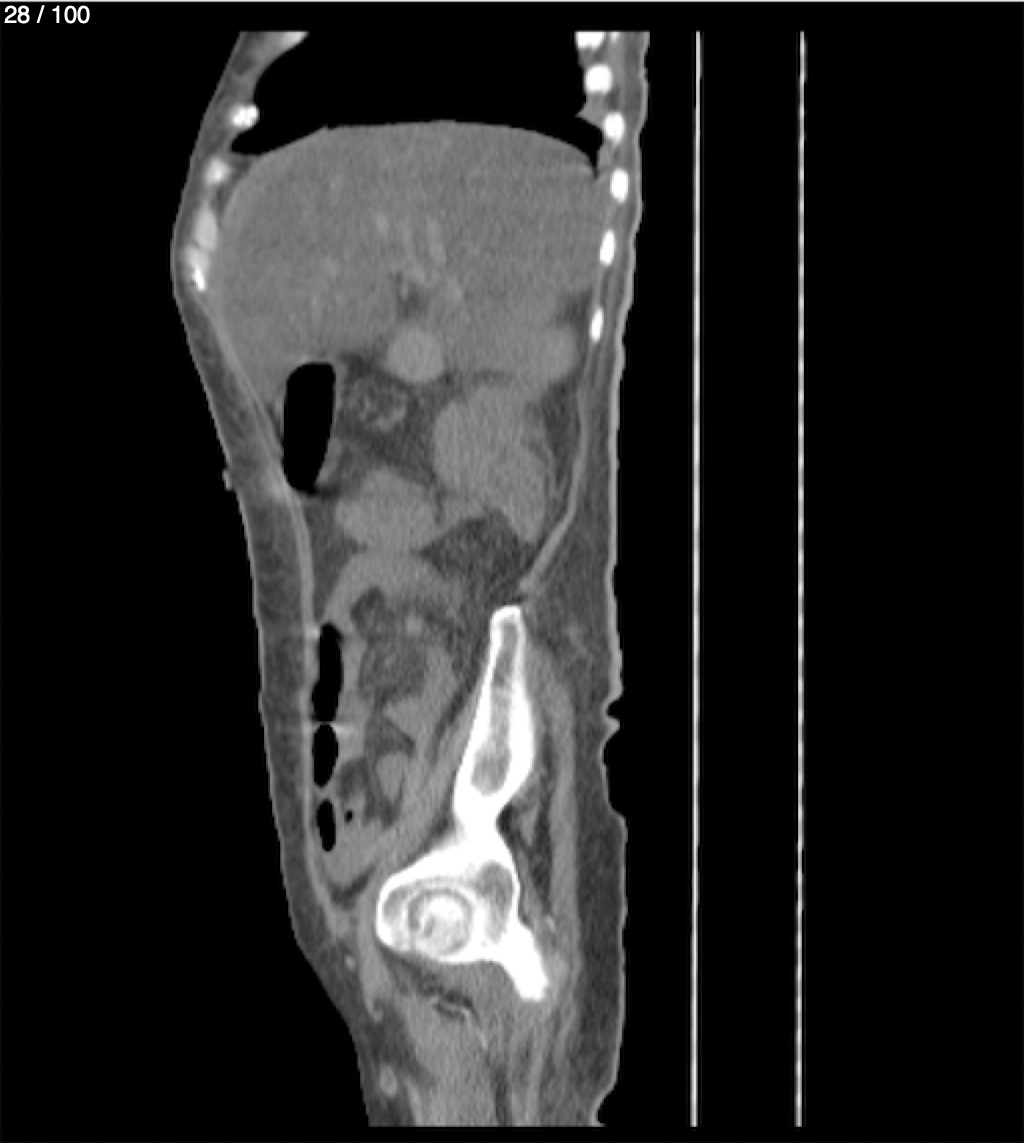

Hilda Geronimo Mendez 60A - T.C Abdomen Simple